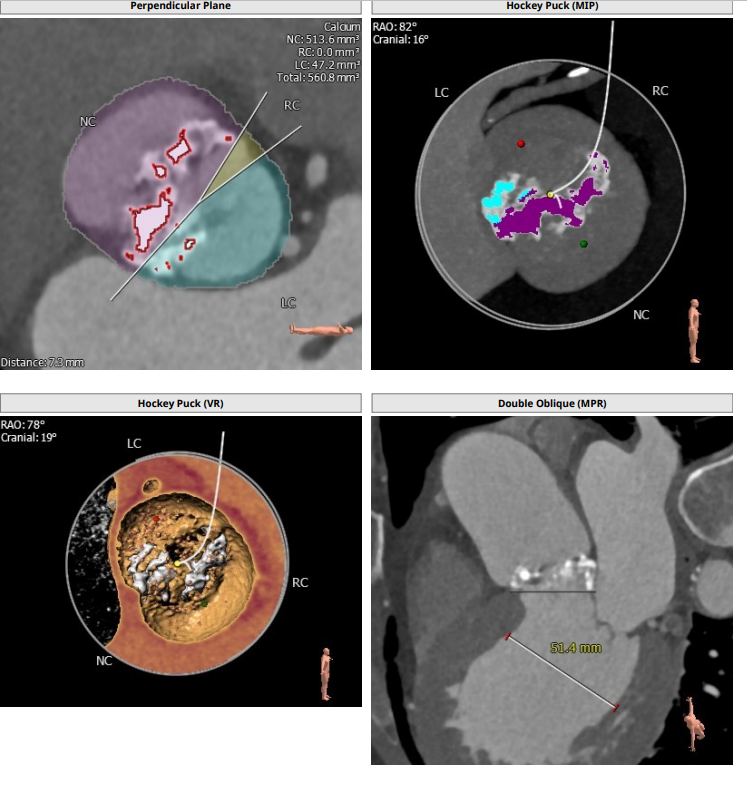

本例患者只有61岁,超声诊断低流速低压差AS,合并升主动脉扩张,CT下测量升主动脉超过50,原则上首选外科手术。但广东省人民医院大血管组会诊后考虑患者低流速低压差,行主动脉瓣和升主动脉置换术,手术风险极高,建议TAVR。从解剖上,瓣环流出道的大小分别是30、31,但瓣上结构是TYPE 0二叶瓣,重度钙化,联合部有钙化融合,瓣上短轴31,窦高度超过23,横位心,角度78°二叶瓣方向呈1点到7点方向。这种解剖做TAVR无疑挑战极大。对于低流速低压差的患者合并解剖挑战的病人,术前计划就是ecmo辅助下TAVR。考虑二叶瓣和重度钙化,目标瓣膜是29号,故用23号球囊预扩,尽量不破坏瓣上结构,另外考虑横位心,升主宽,破裂风险高,瓣膜跨瓣困难,故准备抓捕器辅助跨瓣。投照角度方面准备了瓣膜切线位(左肩),用来跨瓣和球扩,同时准备多一个右足位,这个角度下瓣环和人工瓣膜可以达到共平面,方便瓣膜定位。因为升主宽,横位心,主动脉迂曲,为减少破裂风险,没有选择plus。术中跨瓣遇到较大挑战,因为主动脉根部的角度大,普通的AL2,JR2,多功能导管均无法跨瓣,尝试直头导丝和弯头泥鳅也失败,最后是JL4加直头导丝成功跨瓣。预扩后瓣膜跨瓣尽管在抓捕器辅助下仍然非常困难,在反复尝试后侥幸跨瓣。瓣膜释放后位置偏深,但结合瓣膜角度,瓣周漏可以接受,压差消失,故未再行瓣中瓣。术中未发生停跳,故手术结束后撤去ECMO返回CCU。术后一个月随访EF值明显改善,患者自我感觉明显好转,虽然有中度瓣周漏,但是患者年轻,调整好心功能后,为以后外科置换升主动脉和主动脉瓣打下基础。

患者为type0二叶瓣,重度钙化,78度大横位心,左心明显扩大,EF值为21%,瓣环径为30.1,LVOT31.5,二叶瓣鱼嘴开口初短径为31,钙化融合至对侧为27.5,左右冠高度均为25.7,升主明显扩张。